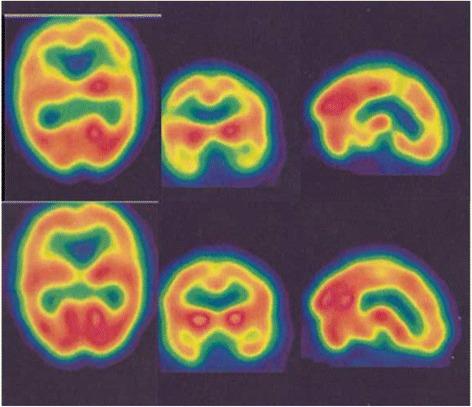

METHODS

We retrospectively reviewed 25 secondary progressive (SP)-MS patients from the hospital database. Neurological disability evaluated by Expanded Disability Status Scale Score (EDSS). Brain perfusion was performed by (99 m) Tc-labeled bicisate (ECD) brain SPECT and the data were compared using statistical parametric mapping (SPM). In total, 16 patients underwent HBOT. Before HBOT and at the end of 20 sessions of oxygen treatment, 99mTc-ECD brain perfusion single photon emission computed tomography (SPECT) was performed again then the results were evaluated and compared. Brain perfusion was performed by (99 m) Tc-labeled bicisate (ECD) brain SPECT and the data were compared using statistical parametric mapping (SPM).

RESULTS

A total of 25 SP-MS patients, 14 females (56 %) and 11 males (44 %) with a mean age of 38.92 ± 11.28 years included in the study. The mean disease duration was 8.70 ± 5.30 years. Of the 25 patients, 2 (8 %) had a normal SPECT and 23 (92 %) had abnormal brain perfusion SPECT studies. The study showed a significant association between severity of perfusion impairment with disease duration and also with EDSS (P <0.05). There was a significant improvement in pre- and post-treatment perfusion scans (P <0.05), but this did not demonstrate a significant improvement in the clinical subjective and objective evaluation of patients (P >0.05).